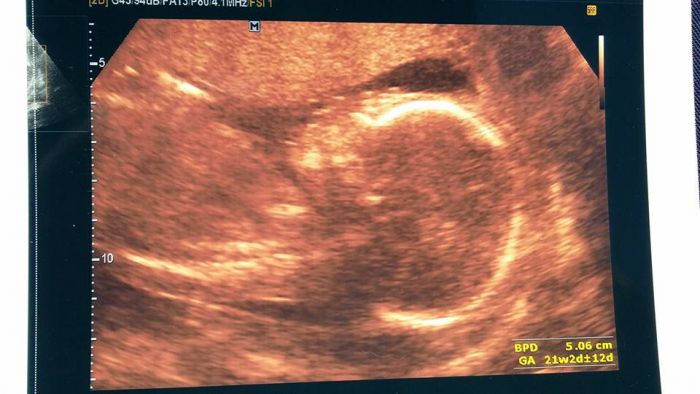

Byli jsme na kontrole na velkém utz a vše v pořádku. Máme už 23cm a vážíme 400g. A pindík už mu na 100% neupadne

Lucko, to se nám u porodu stát fakt nemůže potom, co jsem viděla na tom utz. I paní doktorka říkala, jak na nás hezky ukazuje pindíka a pytlík byl taky krásně vidět. Z toho už se holka neudělá